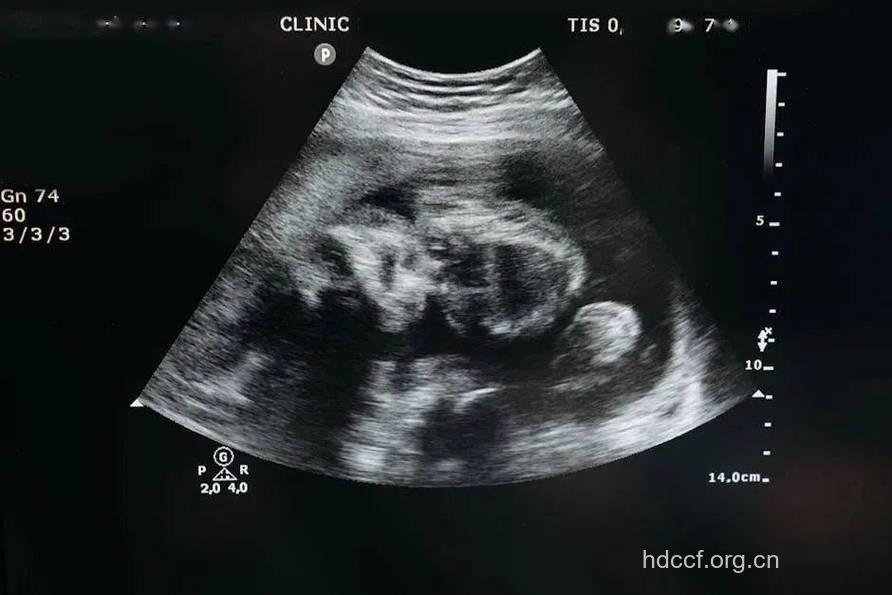

怀孕后,为了及时的了解宝宝的健康发育情况,孕妈妈们需要进行B超检查。B超可以观察妊娠部位是否正常(排除宫外孕),在孕13周后,B超可以清晰地显示出胎儿的内脏器官和四肢骨骼。通过测量所得到的数据,估计胎儿发育情况。还能确定胎位及胎盘位置,评估胎盘功能,选择分娩方式。对于异位妊娠,B超有辅助诊断意义。对于子宫异常增大的孕妇,可以确定羊水过多还是多胎妊娠,观察胎儿有无畸形。若怀疑有染色体异常的遗传病胎儿,可在B超下抽取少量绒毛组织、宫内脐血或羊水,再进一步作遗传学检查。

9周:胎儿长到2.15厘米,胎儿头大于胎体,各部表现更清晰,头颅开始钙化、胎盘开始发育。B超可见胎囊几乎占满宫腔,胎儿轮廓更清晰,胎盘开始出现。

10周:胎儿长到2.83厘米,胎儿各器官均已形成,胎盘雏形形成。B超可见胎囊开始消失,月芽形胎盘可见,胎儿活跃在羊水中 。